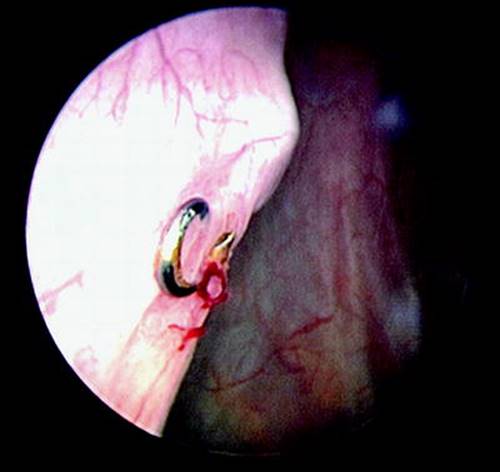

Possible etiologies of de novo urge incontinence include UTI, obstructive voiding, and the presence of a foreign body in the lower urinary tract. In women whose symptoms persist after 6 weeks and post-void residuals are normal, conservative treatment for urge incontinence can be considered including anticholinergics and behavior modifications. A woman who is not responsive or whose symptoms appear severe might benefit from a cystoscopic examination to rule-out the presence of a foreign body in the lower urinary tract. Women, who have undergone a laparoscopic Burch procedure and have evidence of a foreign body in the bladder, may have undergone the procedure using metal helical “tackers” to suspend the bladder neck (Fig. 10.2). These are often placed or migrate into the bladder causing symptoms. If operative notes are not available, then an anterior/posterior and lateral plain X-ray will allow visualization of the offending material.

Fig. 10.2

Cystoscopic view of a metal tacker placed during a laparoscopic Burch colposuspension (photograph courtesy of Howard Goldman, MD, Cleveland Clinic, OH)